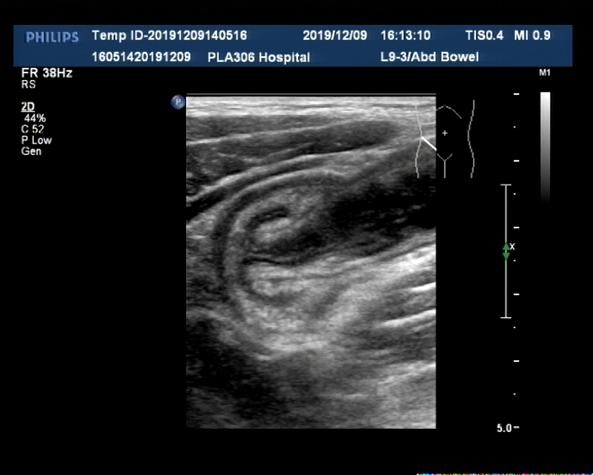

超声表现:腹部可探及包块,横断面呈多层"同心圆"征(图3),纵断面呈多层肠管平行排列的"套筒"征(图4),超声多普勒检查提示包块内血流信号呈点状散在分布(图5);或观察到动静脉频谱,提示肠管受压的症状轻,循环良好,包块内未显示血流信号或血流信号稀少,提示肠管可能存在缺血坏死的症状。部分患儿包块及周围肠系膜内可探及增大的淋巴结(图6)。

图4. 肠套叠纵切套筒征